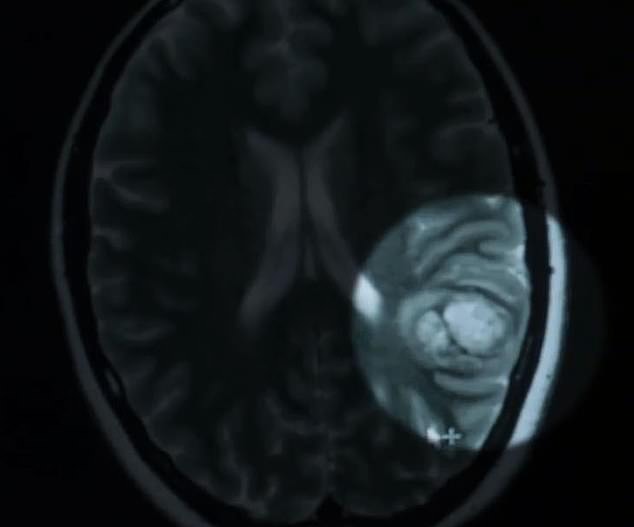

在经过医生的诊断之后,医生判断Jenna患上癫痫的原因,是因为大脑中有一团畸形的纠缠在一起的血管,称为海绵状瘤。(图片显示在右侧)

事实上,这其实并不是什么特别罕见的症状。

这种病虽然少见,但与其它的肿瘤类的畸形状况相比,患上这种海绵状瘤的几率其实还要更高一些。

据估计,大约每100到200人之中,就有一个人会患有海绵状瘤,但大约有四分之一的患者从来没有出现过任何症状。

目前人们还没有发现这种症状出现的原因,只知道这是血管纠缠在了一起。

随着这个肿瘤体积的增长,它会对人类的大脑形成压迫,从而破坏大脑的部分功能,

最终可能导致视力丧失、精神错乱、恶心、头痛、睡眠困难、平衡障碍等一系列问题。